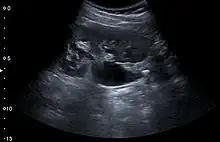

One of the primary indications for referral to US evaluation of the kidneys is evaluation of the urinary collecting system. Enlargement of the urinary collecting system is usually related to urinary obstruction and can include the pelvis, the calyces and the ureter. Hydronephrosis is seen as an anechoic fluid-filled interconnected space with enhancement within the renal sinus, and normally, the dilated pelvis can be differentiated from the dilated calyces.[1]

Figure 13. Hydronephrosis due to ureteropelvic junction obstruction in a pediatric patient.[1]

Several conditions can result in urinary obstruction. In both adults and children, masses, such as abscesses and tumors, can compress the ureter. In children, hydronephrosis can be caused by ureteropelvic junction obstruction, ectopic inserted ureter, primary megaureter and posterior urethral valve (Figure 13). In the latter, both kidneys will be affected. In adults, hydronephrosis can be caused by urolithiasis, obstructing the outlet of the renal pelvis or the ureter, and compression of the ureter from, e.g., pregnancy and retroperitoneal fibrosis. Urolithiasis is the most common cause of hydronephrosis in the adult patient and has a prevalence of 10%–15%.[1]